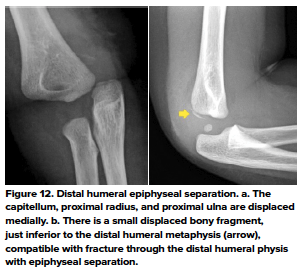

- Distal Humeral Epiphyseal Separation

- This fracture is rare and has been described in children less than 2 years of age. Common mechanisms include FOOSH, traction, and rotary forces. A considerable force is required to cause this fracture, and since young infants are not mobile enough to produce this force, non-accidental trauma must be suspected in these cases. That being said, it can also occur due to birth trauma- both vaginal delivery and cesarean section. The diagnosis can be challenging since the distal humeral epiphysis is cartilaginous and not visualized on x-rays. The most important finding is the posteromedial displacement of the radius and ulna in relation to the distal humerus.12 (Fig. 12)